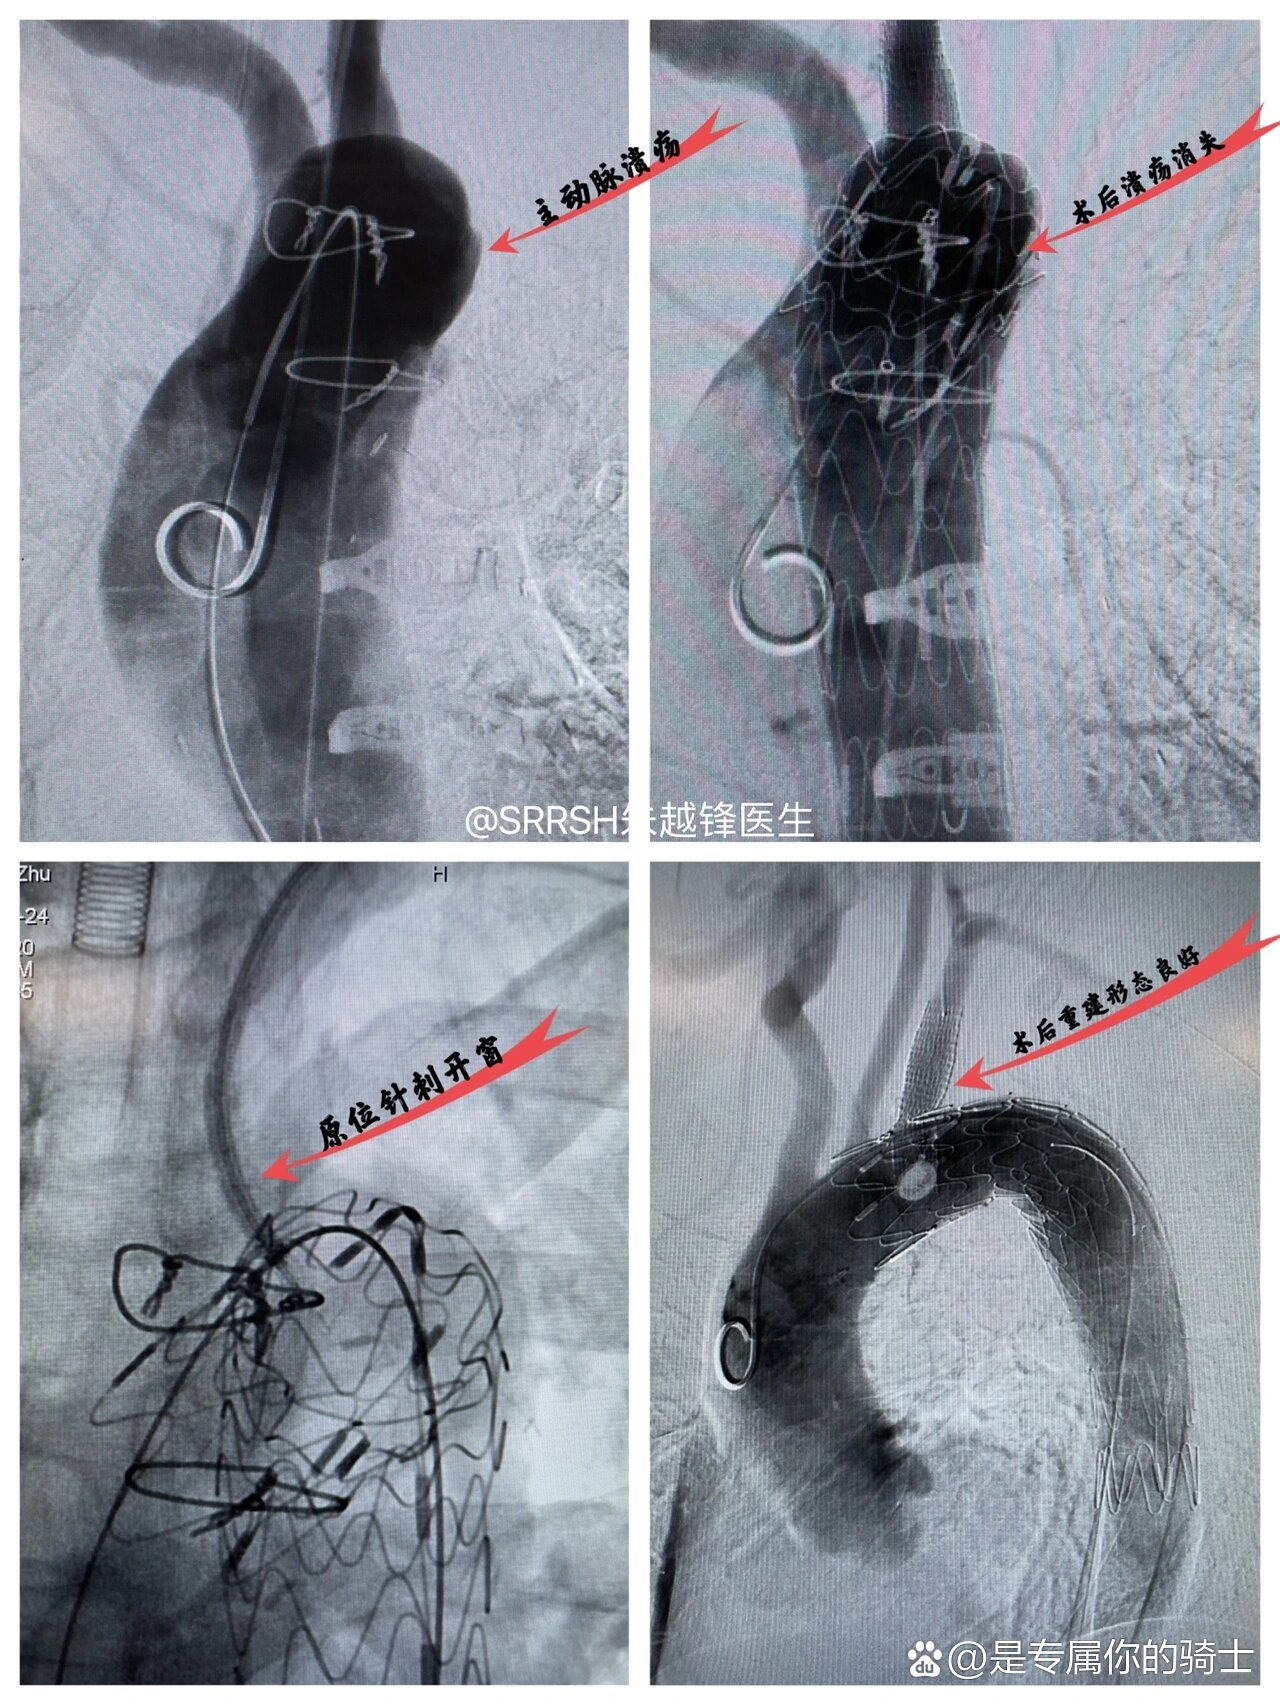

全天门诊,下午抽空顺手做了个主动脉弓部溃疡的腔内覆膜支架修复加左

术前检查▲术后造影手术一个小时,成功为患者行局麻下胸主动脉腔内

心血管内科东院院区采用微创手术救治一名主动脉多发性溃疡患者